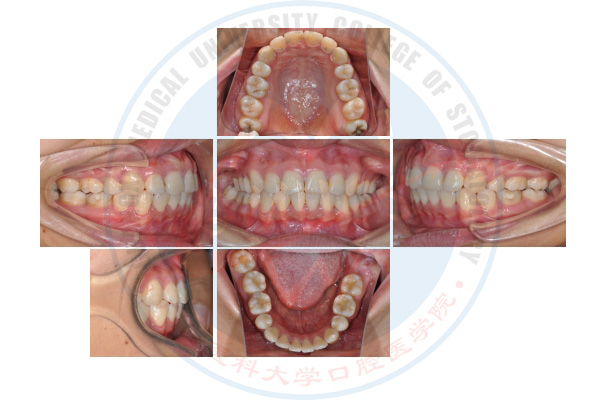

微种植体支抗技术

正畸治疗前

正畸治疗后